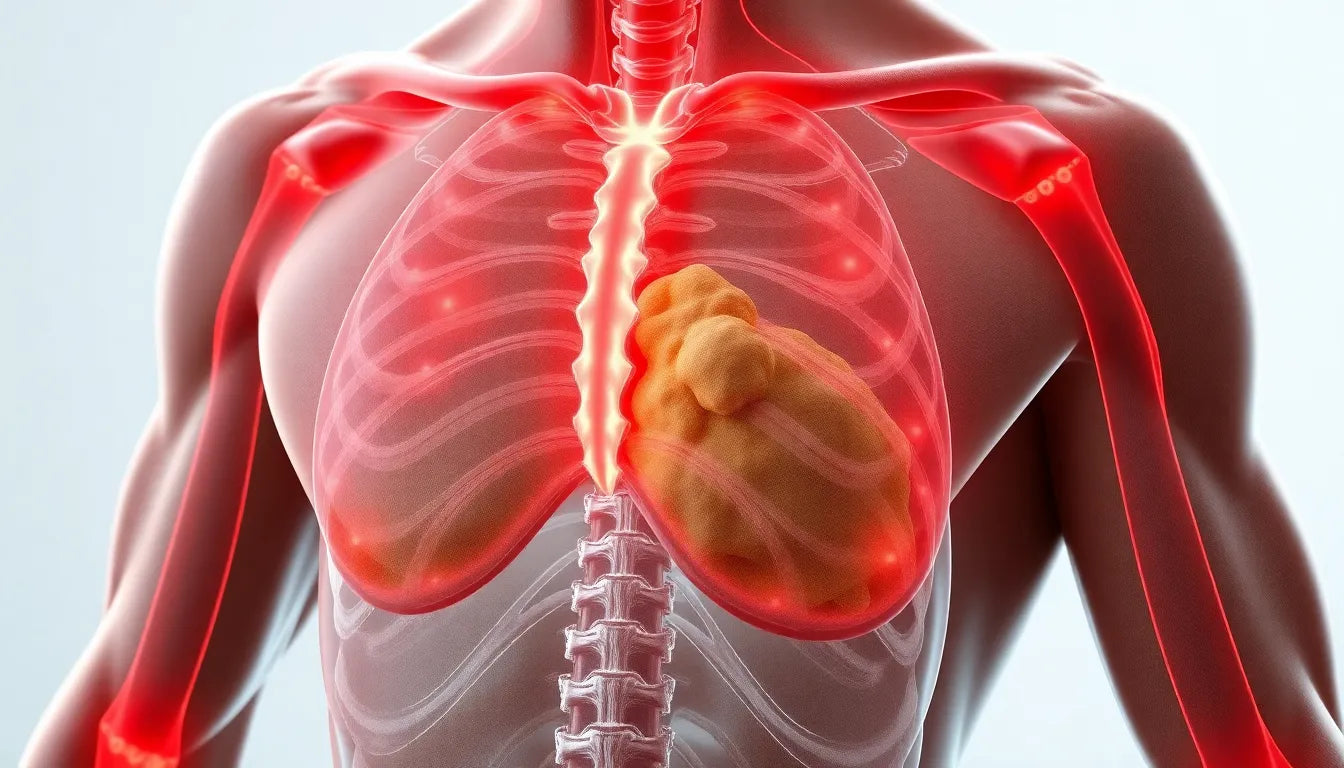

Ondt i ryggen og fryser: hvad betyder det for din sundhed?

Ondt i ryggen og følelsen af at fryse kan være en foruroligende kombination af symptomer. Mens rygsmerter ofte skyldes mekaniske problemer som muskelspændinger, kan kuldefornemmelse pege på en infe...